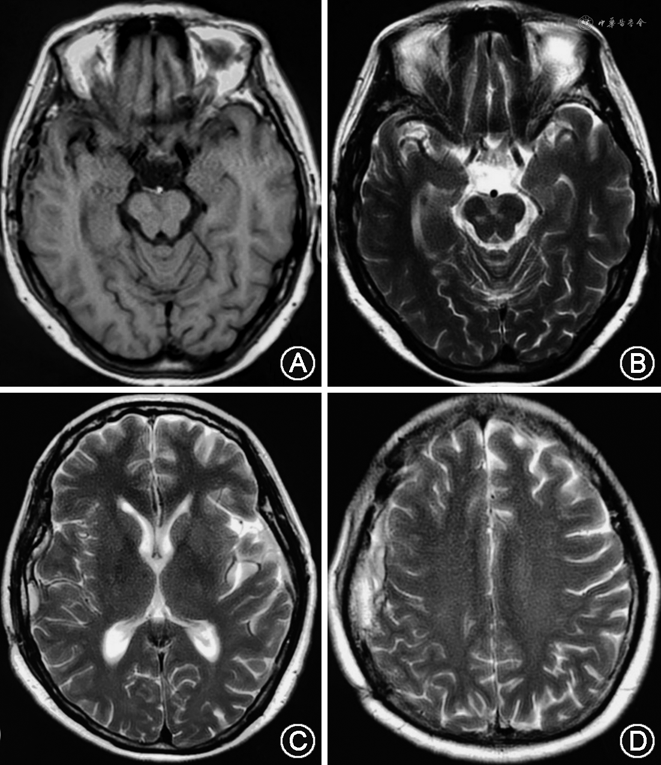

患者女性,55岁,慢性病程。患者自诉于2021年9月初无明显诱因偶发骶尾部疼痛不适感,起初程度轻微,不影响正常生活,后症状迁延,骶尾部疼痛发作频繁且程度加重,严重制约患者日常生活及工作。2021年10月4日入住甘肃省人民医院并于次日完善骶椎MRI检查,结果示骶椎椎管内见一类椭圆形长T1、长T2信号影,长径约2.5 cm(图1)。结合患者病史及影像学资料初步诊断为骶管囊肿。入院体检:骶尾部压痛,其余各项体检结果均未见明显异常。术前完善相关检查,排除手术禁忌证,于2021年10月10日全身麻醉下行后正中入路显微镜下骶管囊肿切除术与脊神经粘连松解术,于麻醉苏醒后返回我科神经重症监护室,予以重症监护,患者嗜睡,轻度恶心,无呕吐,约10 min后患者突发呼之不应,右侧瞳孔散大,直径约5.0 mm,直接及间接对光反射消失,左侧瞳孔直径约2.5 mm,直接及间接光反应灵敏,急予250 ml甘露醇快速静脉点滴并急诊完善头部CT,CT影像学检查结果提示:右侧额顶颞枕部硬膜下血肿,中线由右向左偏移,环池欠清,脑干受压明显(图2)。患者病情危重,遂急在全身麻醉下行右额颞开颅硬膜下血肿清除+骨瓣还纳术,术中未见颅骨骨折、颅内原发性损伤病灶。术后6 h后患者意识状态逐渐恢复,复查头颅CT提示硬膜下血肿清除干净,中线居中,颅内无再出血及梗死表现(图3)。术后采取头高足低位,予以控制颅内压、补液及营养支持等对症治疗后好转离院。定期随访观察并于出院7个月后我院复查头颅MRI提示:右侧额顶颞枕部颅板下片状混杂信号,等T1、长T2信号,脑沟、裂、池未见受压影像,中线结构居中(图4)。患者恢复良好,无明显后遗症。